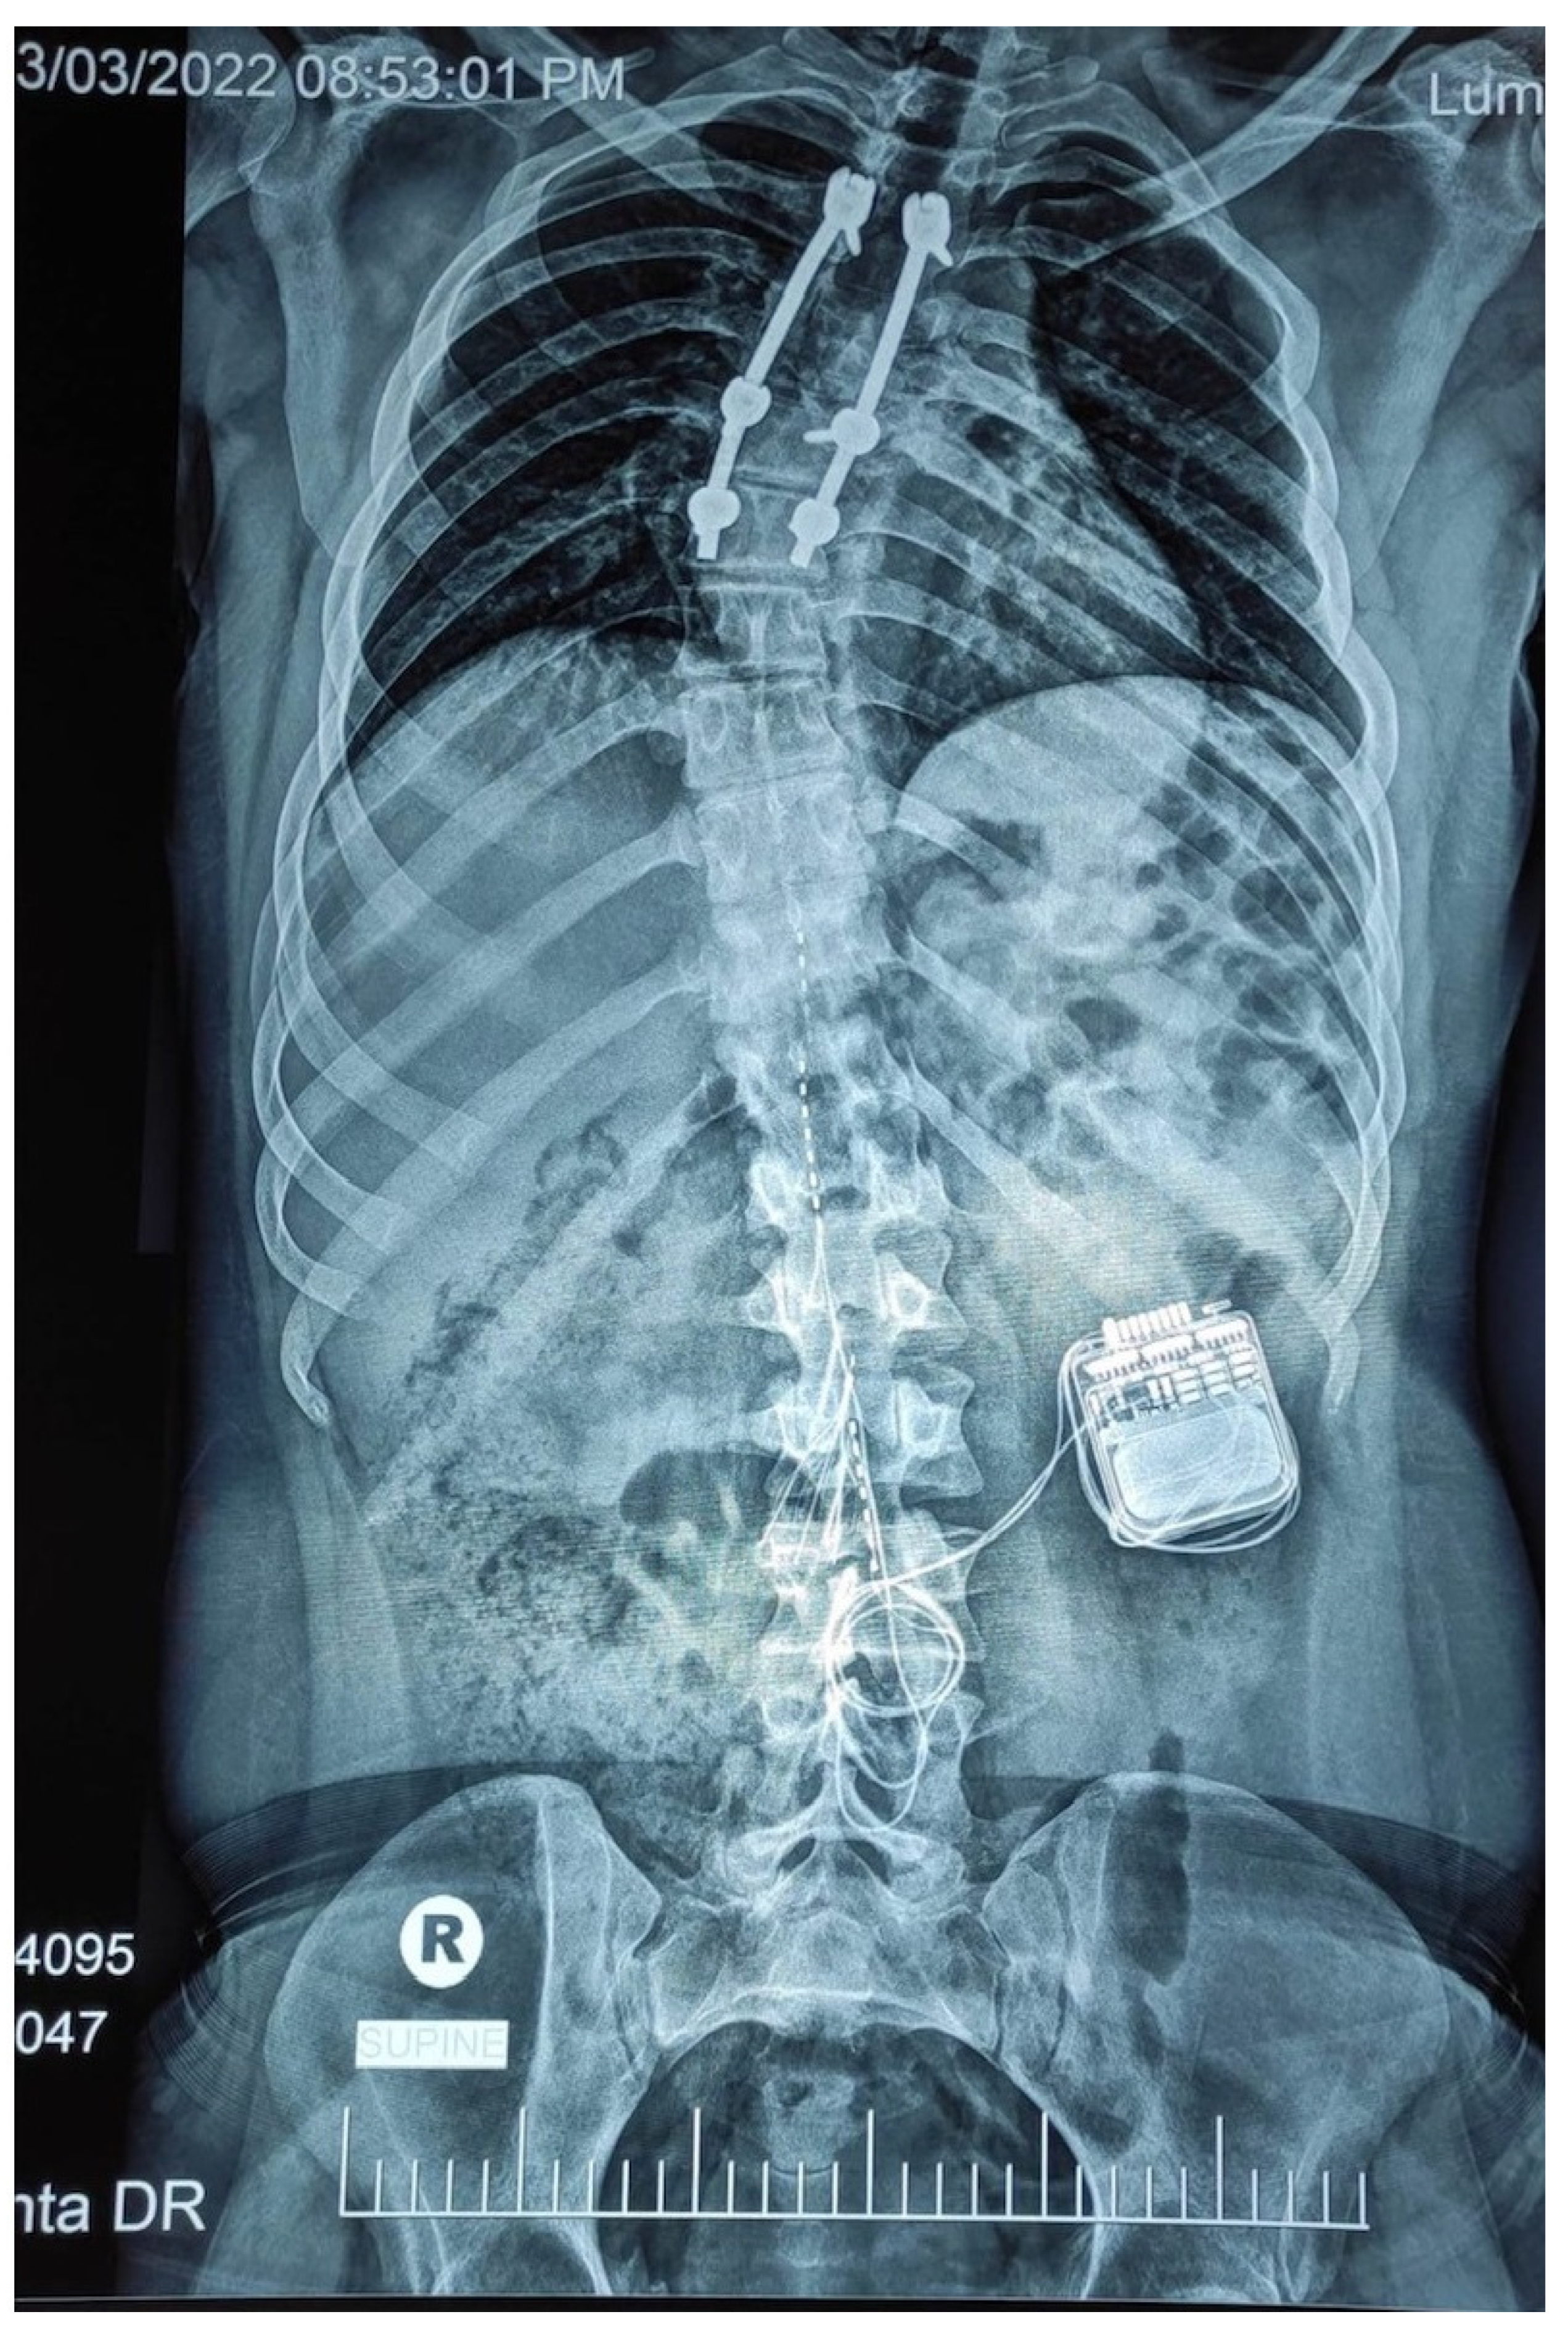

Single Lead Epidural Spinal Cord Stimulation Targeted Trunk Control and Standing in Complete Paraplegia

:1. Case Report